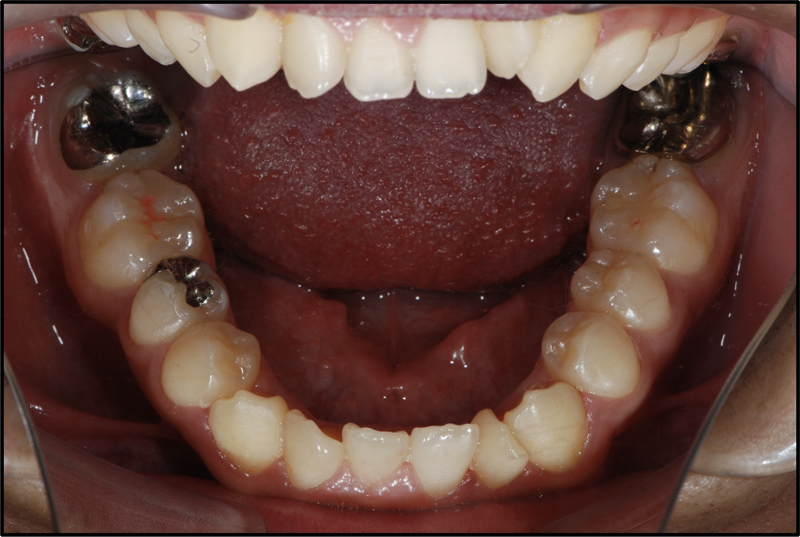

CASE 5 16歳 男

| 悩み | 歯の数が足りないと言われた。 |

|---|---|

| 抜歯 | 上小臼歯1本 |

| 装置 | マルチブラケット(表)、トランスパラタルアーチ |

| 内容 | 右上小臼歯1本、両側下小臼歯が1本ずつ先天欠如していたため抜歯を選択し、3本の先天性欠如を通常の4本抜歯矯正の仕上がりとする治療を行なった。生まれつき歯の本数が少なかった部分の隙間をきれいに閉じることができた。 |

| 期間 | 4年2ヶ月 |

| リスク | う蝕、歯周病、歯根吸収、奥歯の傾斜 |

| 費用 | 70万円(調整料は含みません) |